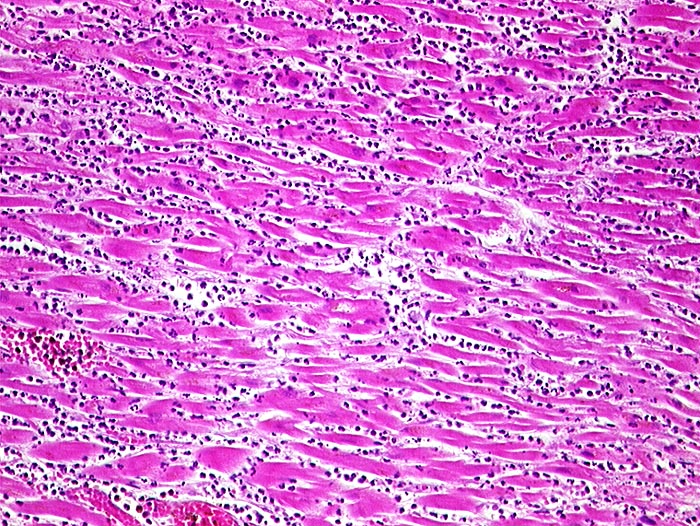

Makroskopie

Pathologischer Befund